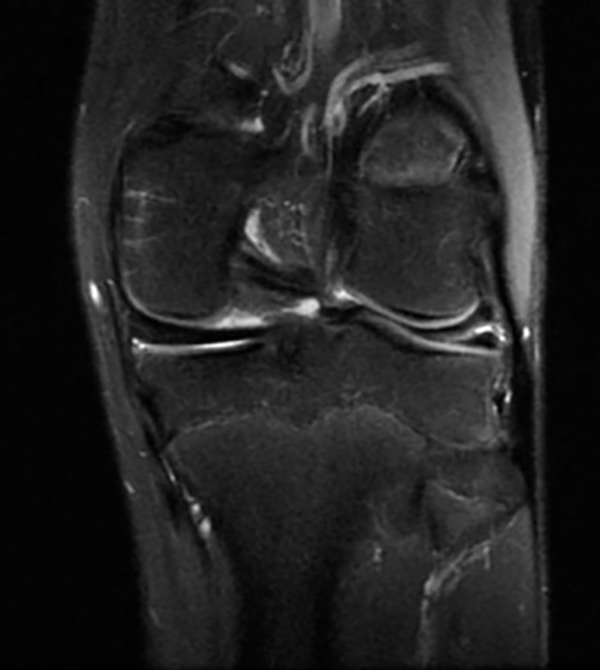

Muchas lesiones complejas comienzan con un componente de lesión horizontal. Por lo tanto, es importante arribar a un diagnóstico certero para instaurar un tratamiento temprano y evitar futuras complicaciones. Además, predisponen a la formación de quistes parameniscales.1 Se observan con mayor frecuencia en el cuerno posterior del menisco medial o en el cuerpo del menisco lateral (fig. 1).

Figura 1: RM de rodilla izquierda. Lesión horizontal del menisco externo.

En estudio de resonancia magnética se cuantifica la lesión meniscal horizontal para tratarla artroscópicamente (ver la fig.1).